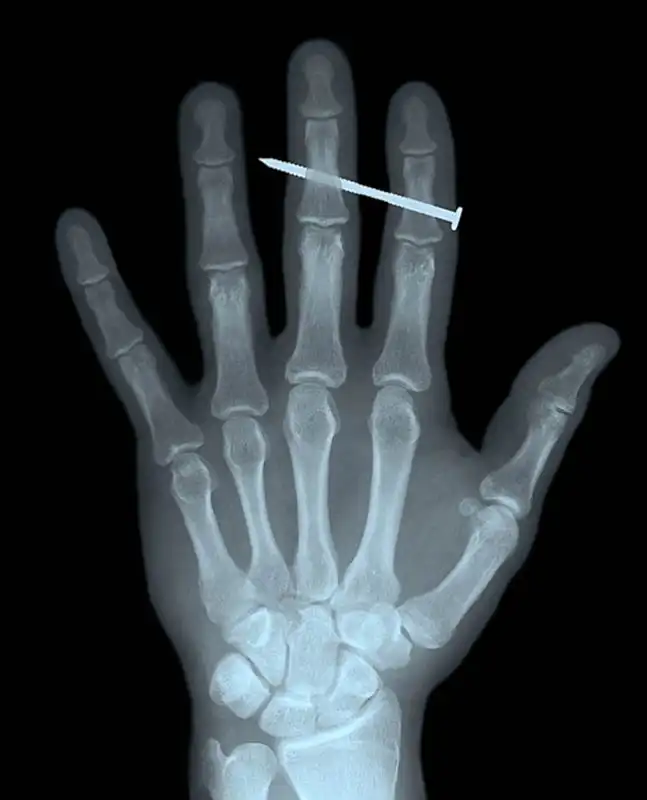

Гвоздь в костях указательного и среднего пальцев взрослого мужчины.